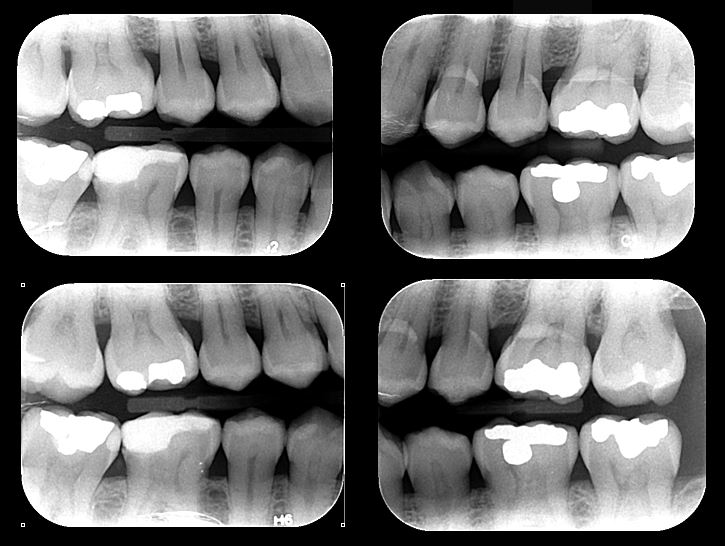

- Radiografías Bite-Wing: Radiografía que permite evaluar en detalle la corona de un diente con la finalidad de diagnosticar caries interproximales, desajuste de restauraciones, pérdida ósea y demás.

Se utilizan principalmente radiografías periapicales, Bite-Wing y oclusales, cada una con funciones específicas para evaluar diferentes estructuras y patologías en la cavidad oral.

Esta radiografía es útil para detectar caries interproximales, evaluar desajustes en restauraciones y valorar la pérdida ósea en los dientes.